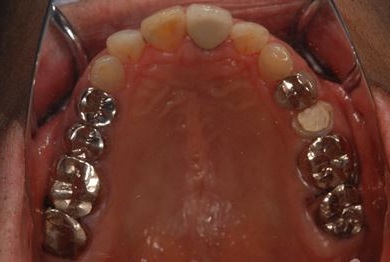

| 性別/年齢 | 男性 / 69歳 | ||||||||||||||||||||||||||||||||

| 主訴 | 1.左上奥歯の詰め物が取れた 2.左上前歯の欠け 3.右下奥歯の欠け | ||||||||||||||||||||||||||||||||

| 治療方針 | セラミック治療にて、審美的回復を行う。 | ||||||||||||||||||||||||||||||||

| 治療内容 | メタルボンドセラミッククラウン1本(メタルボンド用土台1本)、ハイブリッドセラミックインレー1本 | ||||||||||||||||||||||||||||||||